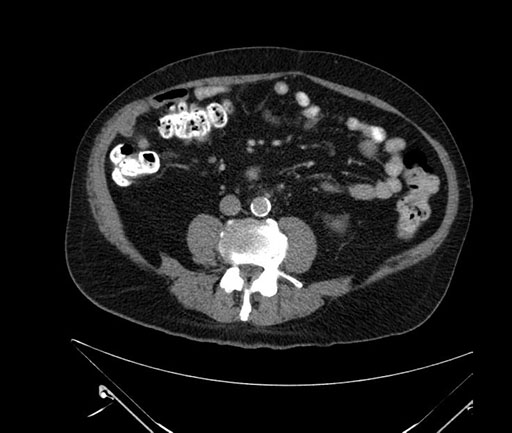

Whipple (pancreaticoduodenectomy) [case 7]

Imaging Analysis

Look through the patient's CT scan to identify any areas of concern for the necessary procedure.

Based on your CT findings, which issue(s) would give reason for "planned slowing down moment(s)" in this case?

Considering a standard Whipple procedure, what step(s) of the operation would you do differently in this case?